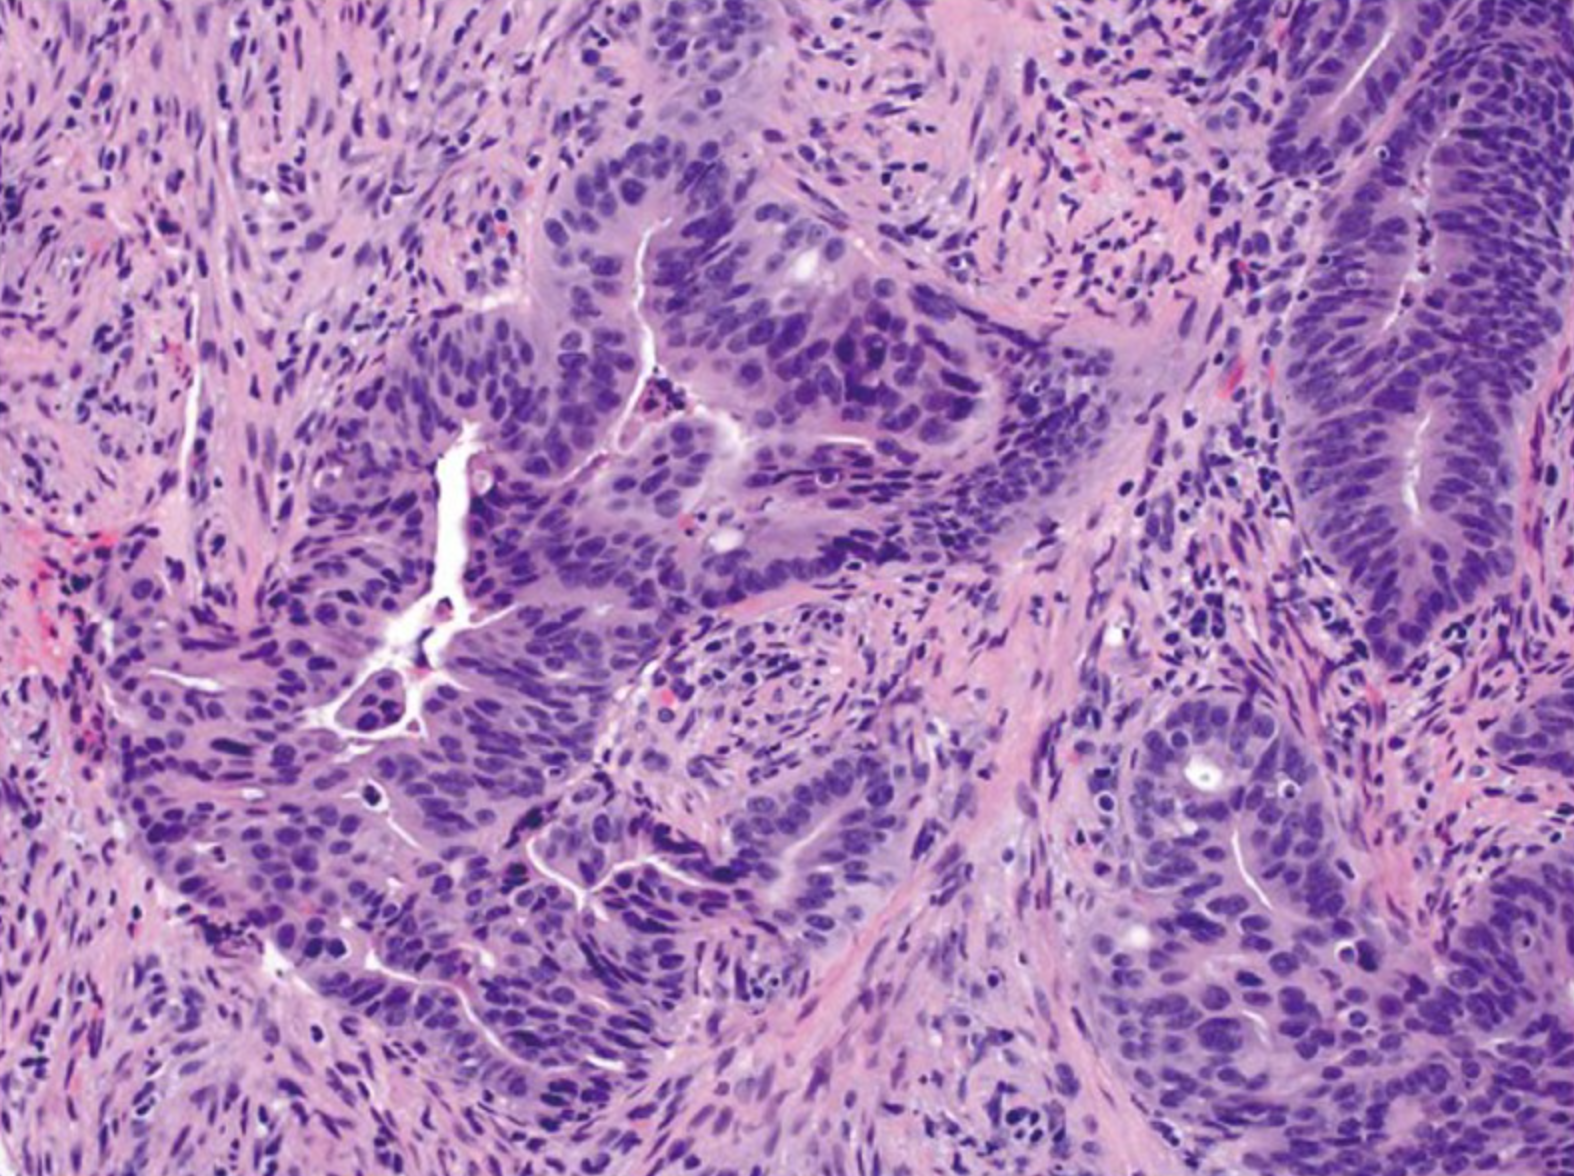

超过90%的结直肠癌是起源于结直肠粘膜上皮细胞的腺癌(adenocarcinoma)。 其他罕见类型的结直肠癌包括神经内分泌细胞癌(neuroendocrine)、鳞状细胞癌(squamous cell)、腺鳞状细胞癌(adenosquamous)、梭形细胞癌(spindle cell)和未分化癌。 常规腺癌以腺状结构为特征,这是肿瘤组织学分级的基础。在高分化腺癌>中,95%的肿瘤是腺形成的。 中分化腺癌显示50-95%的腺体形成。低分化腺癌多为实性,腺体形成率小于50%。 在实践中,大多数结直肠腺癌(约70%)被诊断为中分化(图2)。高分化癌和低分化癌分别占10%和20% [4]。下面将主要介绍几种腺癌的类型。

若本图无法展示,请更换浏览器查看

图2.中等分化腺癌例,在间质间质中可见复杂的腺体结构(放大原图×200) [4]。